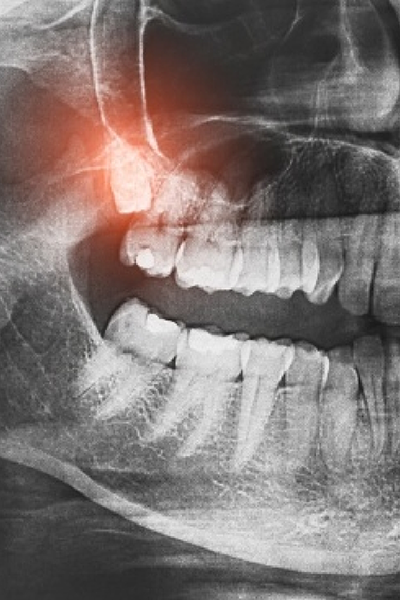

Surgical extractions become necessary when teeth haven’t erupted fully, have broken off at the gum line, have curved or multiple roots, or are impacted beneath bone and tissue. These more complex procedures require incisions in the gum tissue, possible bone removal, and sometimes sectioning the tooth into pieces for extraction. Surgical extractions typically involve longer procedure times and more extensive healing compared to simple extractions.

The distinction between simple and surgical extractions isn’t always clear-cut, as procedures may involve elements of both depending on specific circumstances. Dr. Lim evaluates each tooth individually using clinical examination and X-ray imaging to determine the most appropriate extraction technique. His surgical expertise ensures even complex extractions are performed efficiently with minimal trauma to surrounding structures.

When wisdom teeth don’t have sufficient room to erupt normally, they become impacted wisdom teeth, remaining partially or fully trapped beneath the gum tissue or within the jawbone. Impacted tooth positions can vary, with teeth angled toward other teeth, angled backward, lying horizontally, or growing at various problematic angles. This impaction creates numerous potential complications, including severe pain, infection, damage to nearby tooth roots, cyst formation, and crowding of other teeth as the wisdom tooth attempts to emerge.

Your tooth extraction begins with a thorough discussion of the procedure, anesthesia options, and post-operative care instructions so you know exactly what to expect. We’ll review your medical history, current medications, and any concerns you have about the procedure. X-rays help Dr. Lim plan the extraction approach and identify any anatomical considerations like nerve proximity, root configuration, or bone density that might influence the procedure.

Rarely, nerve injury can occur during the extraction of lower wisdom teeth positioned near nerves that provide sensation to the tongue, lower lip, and chin. While most nerve injuries heal spontaneously within weeks to months, some may result in prolonged or permanent altered sensation. Dr. Lim’s careful surgical technique and thorough pre-operative planning using 3D imaging minimize this already rare risk. Other potential complications include excessive bleeding, jaw stiffness, or damage to nearby teeth, though these occur infrequently with proper technique.